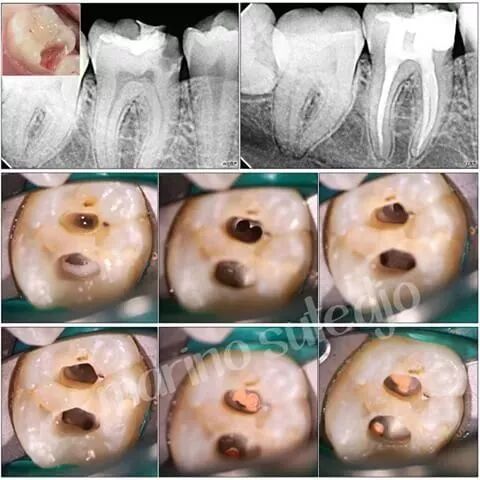

根管治疗通常是由牙髓专科医师或全科牙医来完成的,一般需要就诊1-3次。下面讲解一下步骤:

首先,需要拍x光确定病损的范围,然后接受局部麻醉来控制疼痛,牙疼在牙齿已经发生了脓肿的时候可能会非常剧烈。接下来你的牙齿上会被放置一块类似橡皮布的东西来保持牙齿在治疗中不会沾染你的唾液。龋坏的牙齿组织会被去除,牙齿上方会被打开一个开口以便牙医能够进入你的牙髓所在,并运用各种小器械将感染的牙髓去除。

在感染牙髓被移除以后,髓腔和根管是清洁的,通常还需要对根管进行塑形,为后续的治疗做好准备。在根管被永久充填以前,牙医会对根管进行彻底的消毒和干燥,这个过程中有时会用一些药物充填到根管中来。也有的时候牙洞会开敞上几天,以便于牙齿内的感染物质能够流出来。当感染已经不仅局限于牙齿时,牙医会给你开具抗生素。如果根管治疗需要多次就诊,一般会在牙洞里使用临时充填材料封闭,以保证牙齿不被污染。在牙齿治疗彻底完成以前尽量避免用这颗牙齿嚼东西。

在彻底的清洁和干燥以后,要对牙齿内部的根管进行充填。进行到这一步骤时,往往已经不再需要对牙齿进行麻醉了。临时充填物会被去除,封闭用的糊剂和橡胶成份的混合物会被填塞进牙齿中,这叫做根管充填,简称根充。根充之后,再次把牙齿补上,防止根管受到唾液的影响。